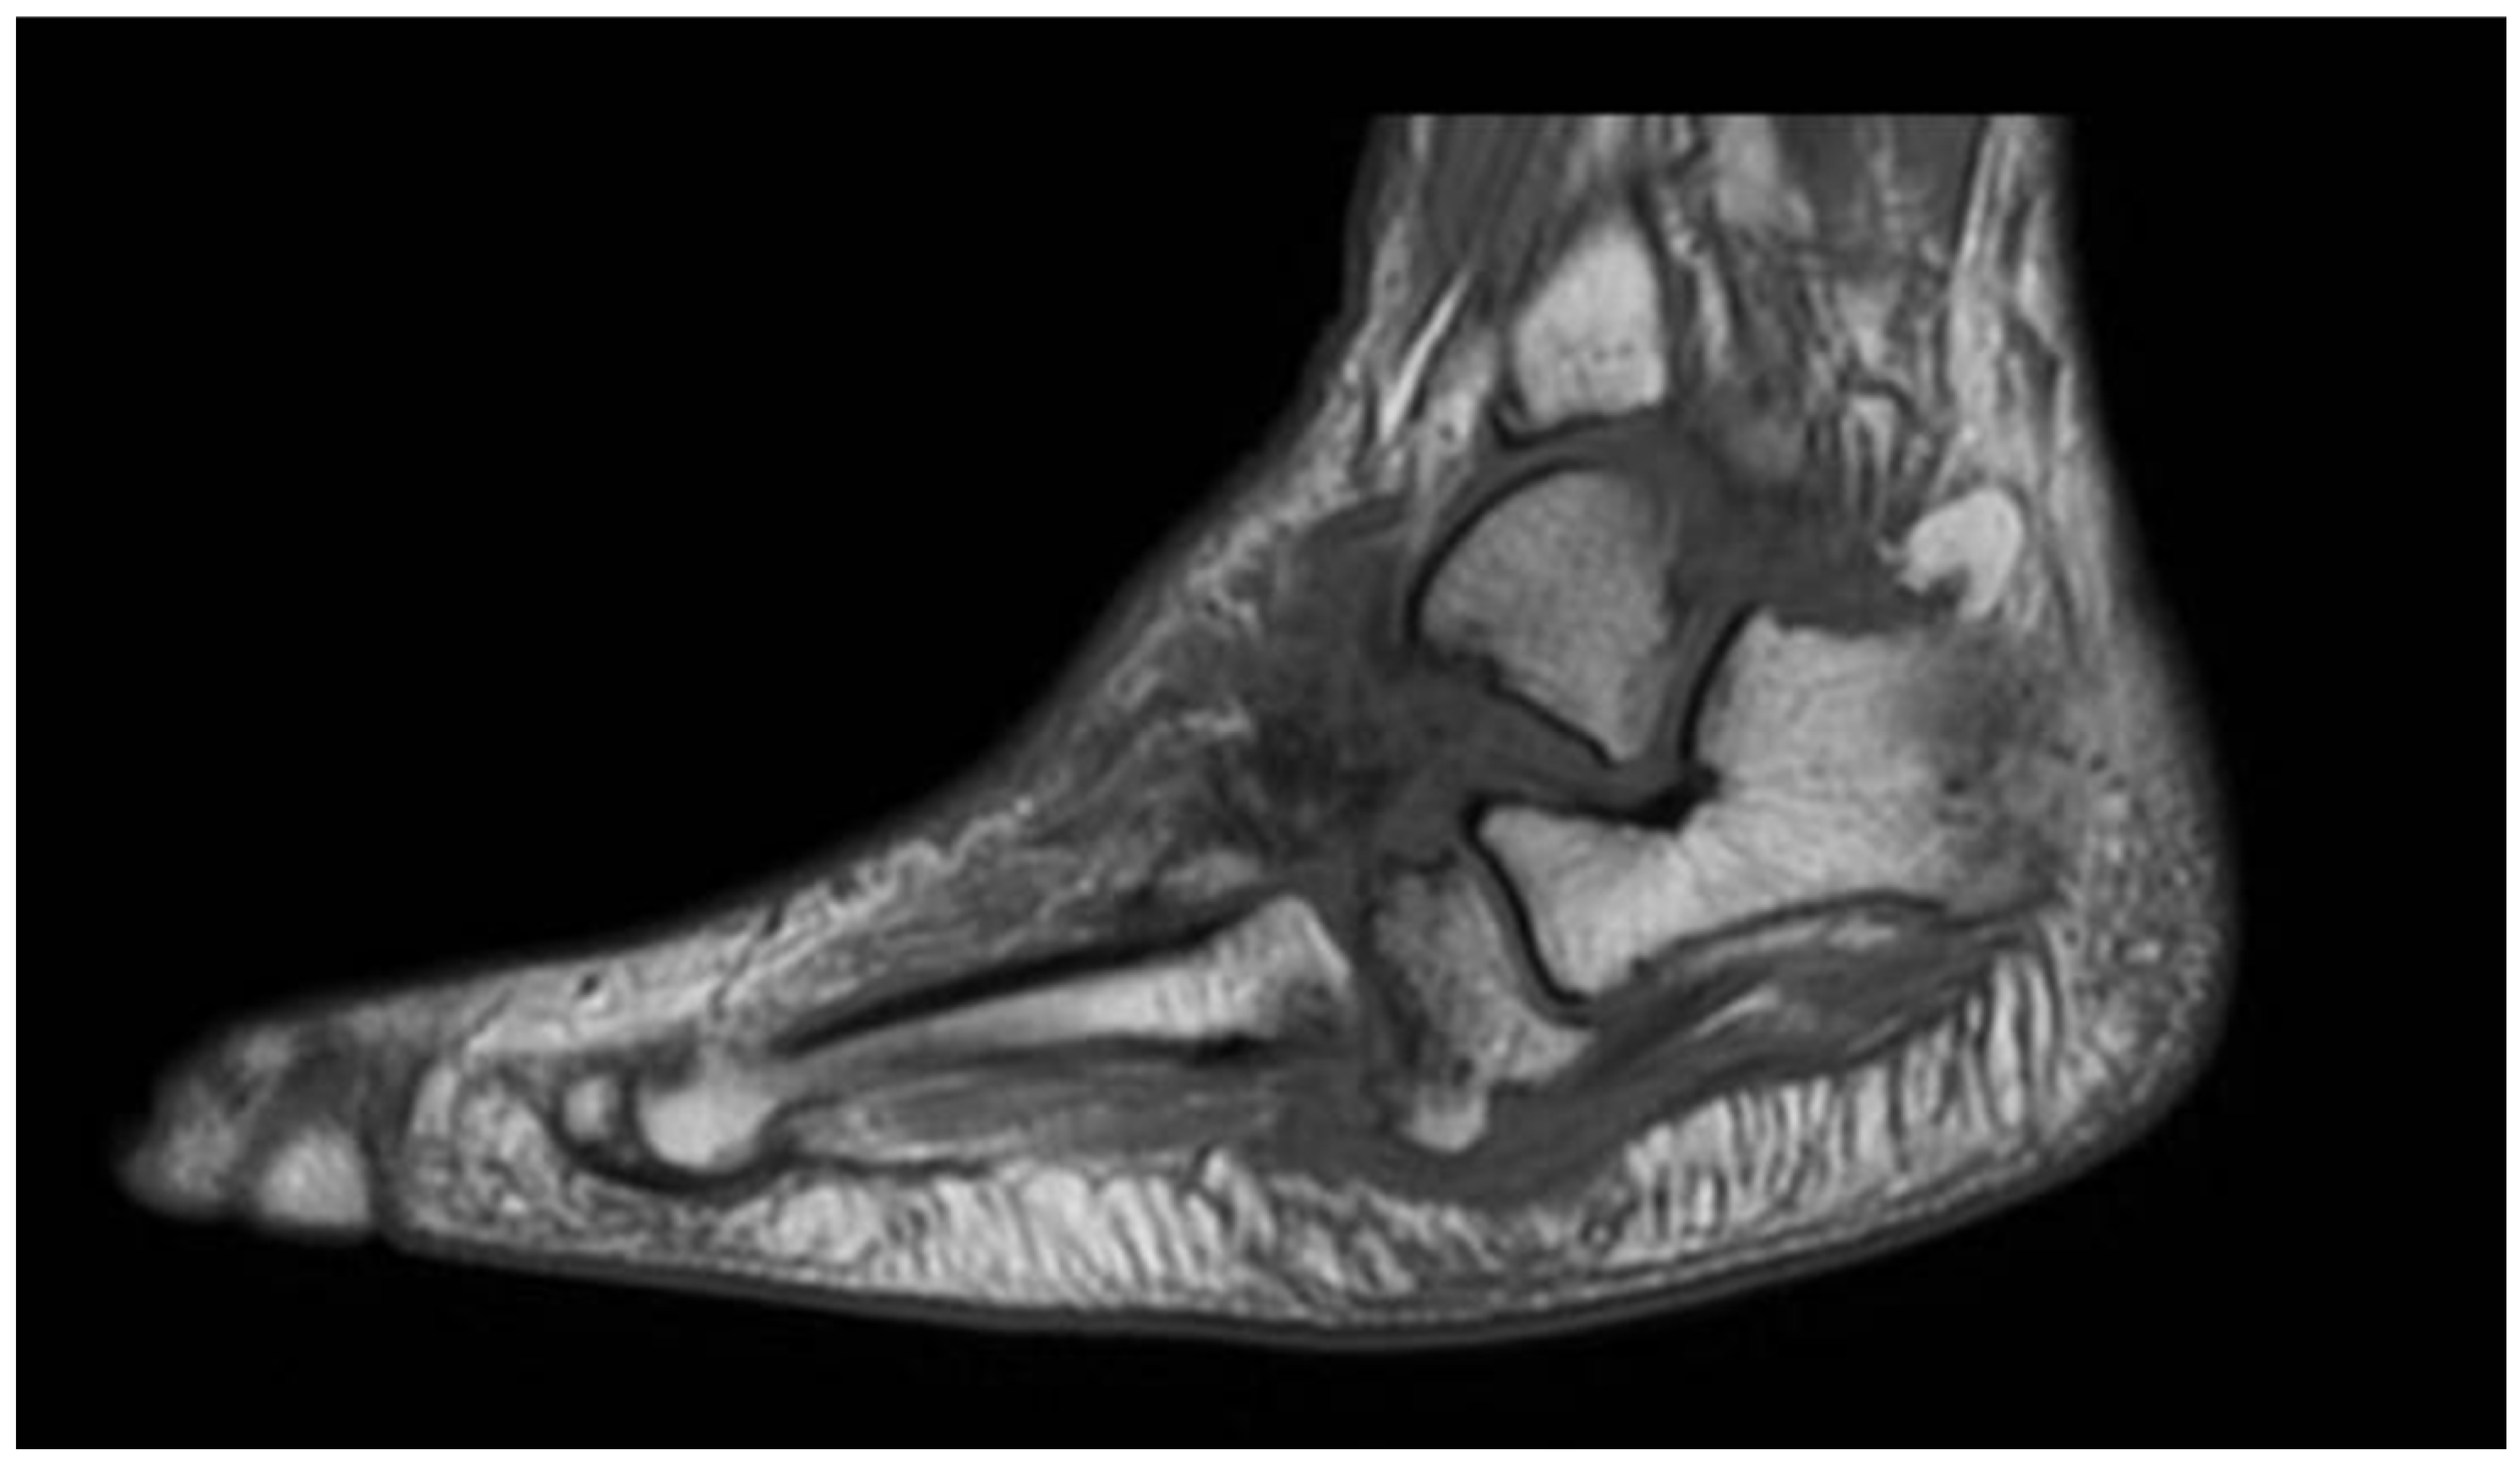

4. Magnetic Resonance Imaging